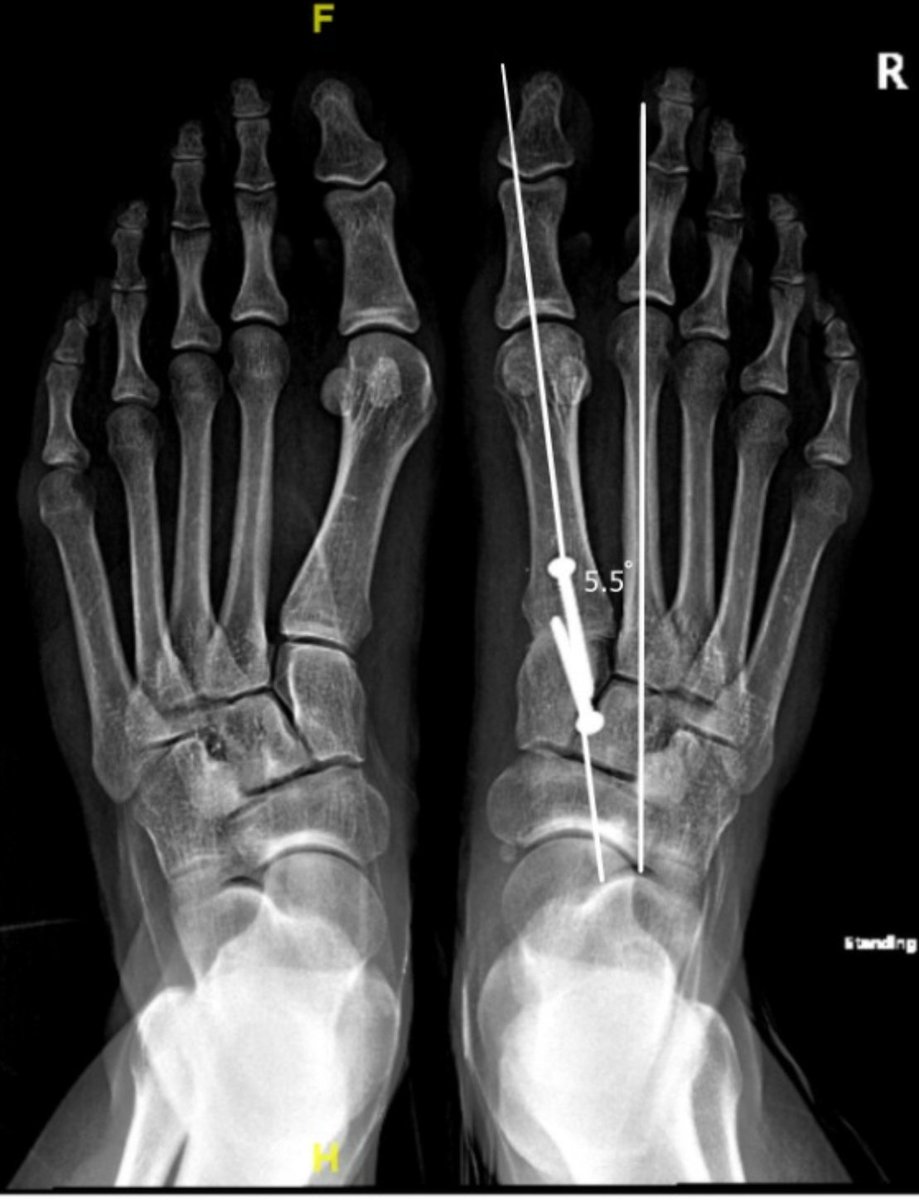

الأشعة:

- توضح درجة الانحراف

- انحراف بالمشط الاول للقدم

6️⃣العلاج الجراحي:

- يعتمد على درجة الانحراف و وجود مرونة في مفصل المشط الأول بالقدم

-الهدف من الجراحة هو إعادة استقامة المشط الاول و استقامة الأصبع الكبير